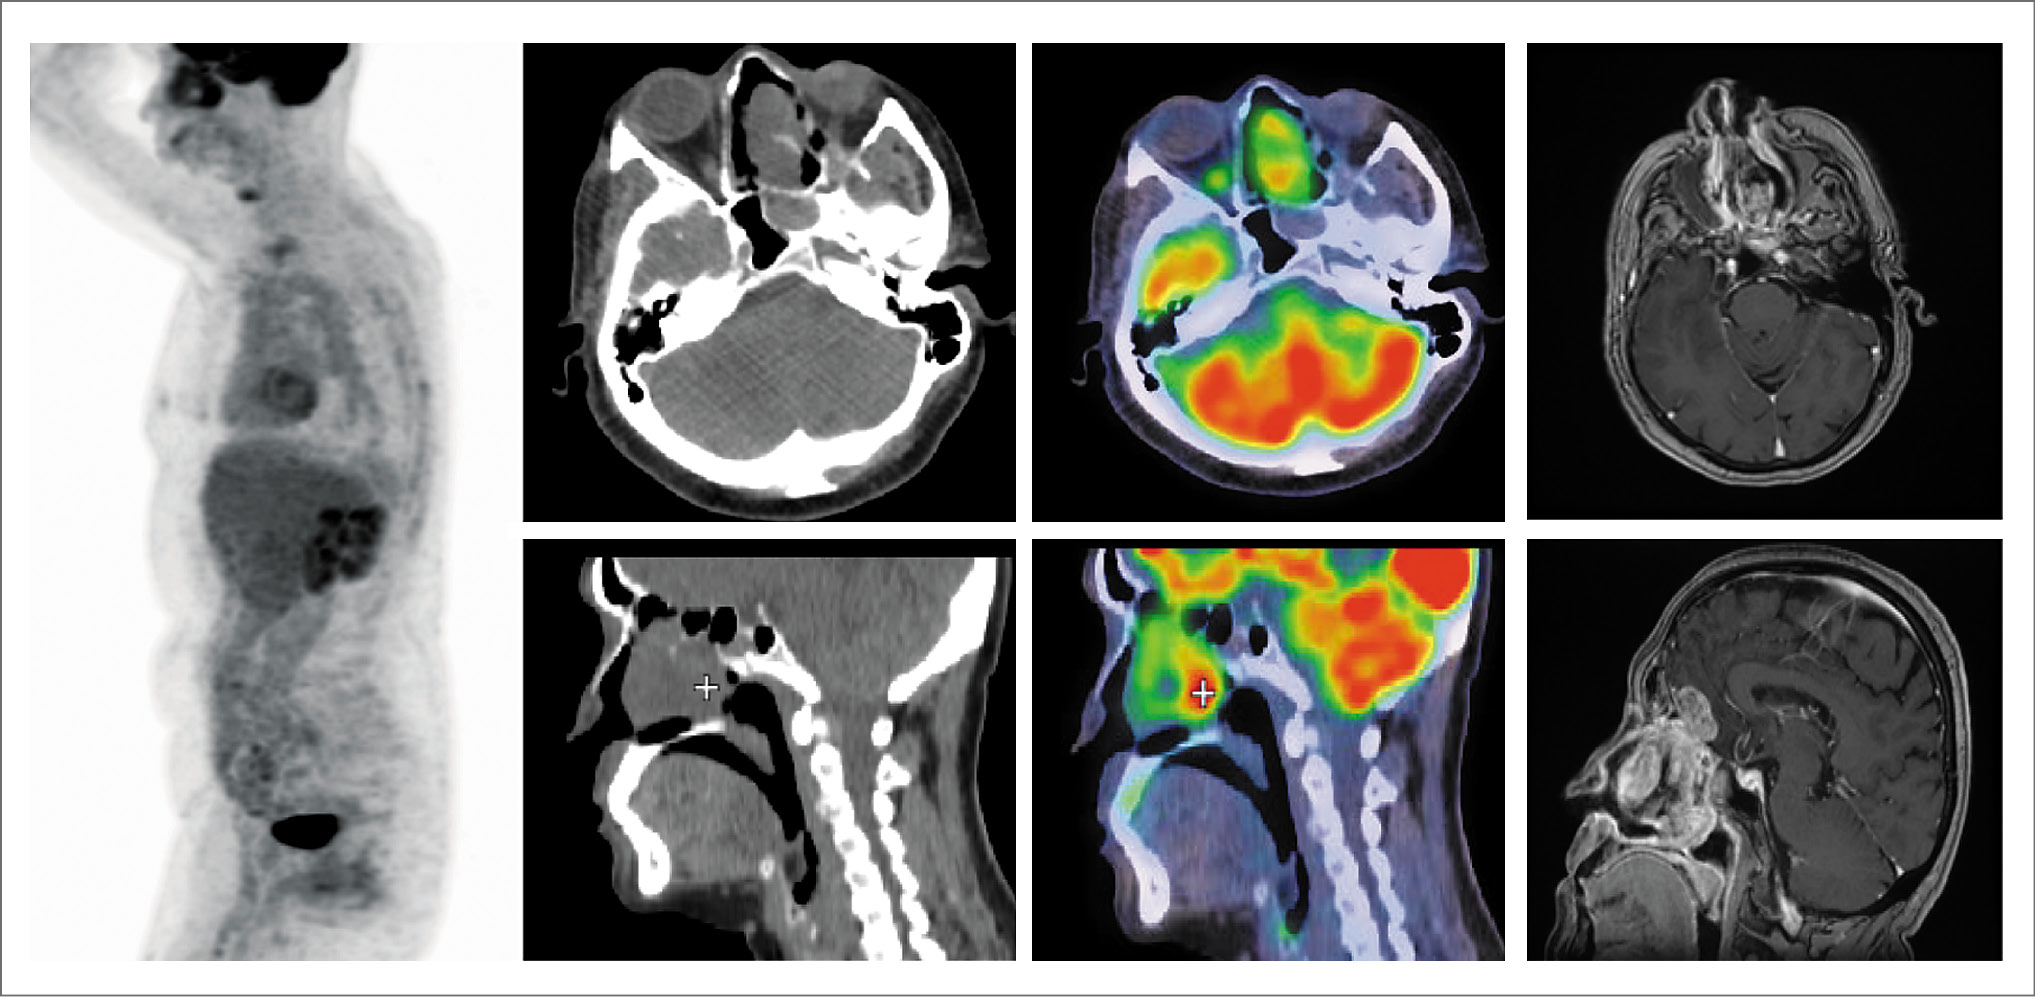

Ниже нами приведены иллюстрации результатов ПЭТ/КТ с 18F-фтордезоксиглюкозой на этапе диагностики и оценки эффекта проводимой терапии.

Через 8 нед с целью оценки эффекта проведенной терапии выполнена ПЭТ/КТ с 18F-фтордезоксиглюкозой. В полости носа сохраняется объемное образование неправильной формы с четкими неровными контурами размером до 51×31×50 мм (ранее 83×38×77 мм) с повышенным поглощением ФДГ SUVmax 3,81 (ранее SUVmax 4,22), с распространением на ячейки решетчатой кости, носоглотку и переднюю черепную ямку. Медиальная стенка левой глазницы истончена, с нечеткими контурами. Глазные яблоки, зрительные нервы и ретробульбарные пространства не изменены. Эффект расценен как частичная регрессия опухоли (рис. 3).

Рис. 3. Пациентка М., 67 лет. Через 8 нед по окончании лучевой терапии, СОД 66 Гр. Частичная регрессия опухоли. На MIP ПЭТ, ПЭТ/КТ на аксиальных и сагиттальных КТ и ПЭТ/КТ проекциях в полости носа сохраняется объемное образование неправильной формы, с четкими неровными контурами, размером до 51×31×50 мм, с гиперметаболизмом ФДГ SUVmax 3,81, с распространением на ячейки решетчатой кости, носоглотку и переднюю черепную ямку.